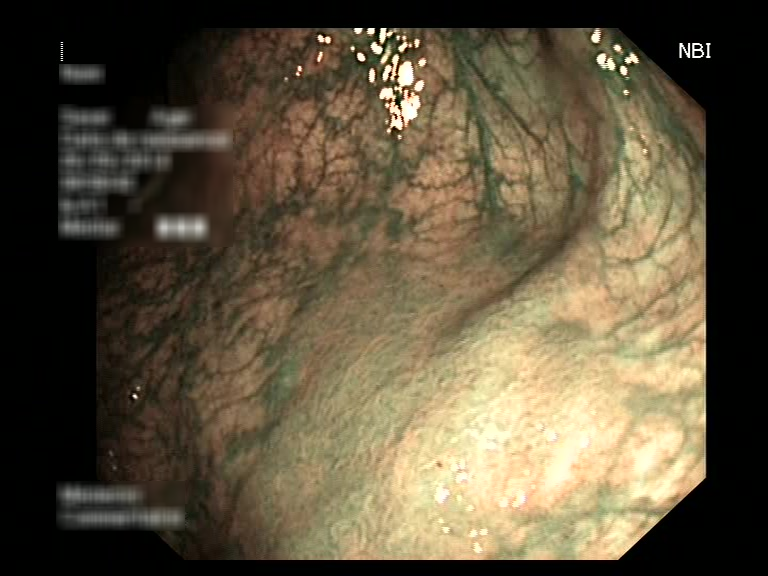

| Lesion | White Light Frame | NBI Frame | White Light Video | NBI Video | Camera Calibration |

| serrated_01 |  |

|

WL.mp4 | NBI.mp4 | cam.xml |